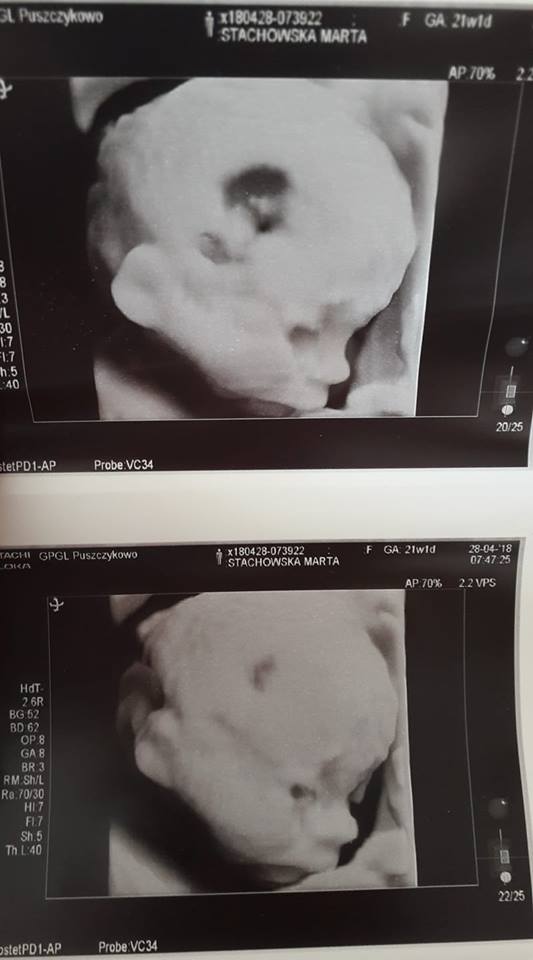

my o 7.30 dzisiaj już byłyśmy na badaniu prenatalnym, mała waży niecałe 500gram :)

i termin na 1.9. Dzieci do szkoły a ja na porodówkę ;)

• 31478667_10155914409093692_4861989819015757824_n.jpg

31478667_10155914409093692_4861989819015757824_n.jpg

38,6 KB · Wyświetleń: 124